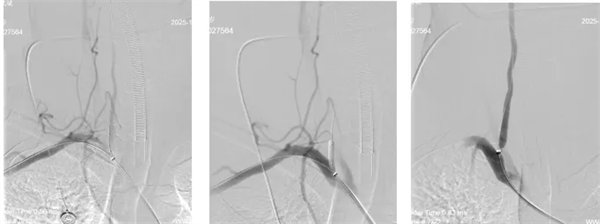

时间就是大脑!在与病人家属充分沟通后,神经内三科介入团队对患者进行了全麻下:颅内动脉取栓术+颅内动脉球囊扩张+椎动脉扩张+椎动脉支架植入术。

术中,介入团队精准定位血管闭塞部位,通过微导丝“探路”联合球囊扩张技术开通右侧椎动脉开口,造影椎开口残余狭窄60%。基底动脉血栓形成,基底动脉管腔狭窄55%,基底动脉尖堵塞,右侧大脑后动脉及小脑上动脉未见显影,左侧大脑后动脉P3以远闭塞。

席聪准确锁定患者基底动脉处血栓,采用抽吸取栓技术快速开通血管,成功取出堵塞部位2cm的血栓。再次造影示:右侧大脑后及双侧小脑上动脉再通,右侧大脑后动脉P3段以远闭塞,考虑慢性闭塞,推注替罗非班,血流明显加快。随后采用支架植入术开通右侧椎动脉开口处,术中影像显示:支架贴壁良好,无明显残余狭窄,颅内血管显影良好。